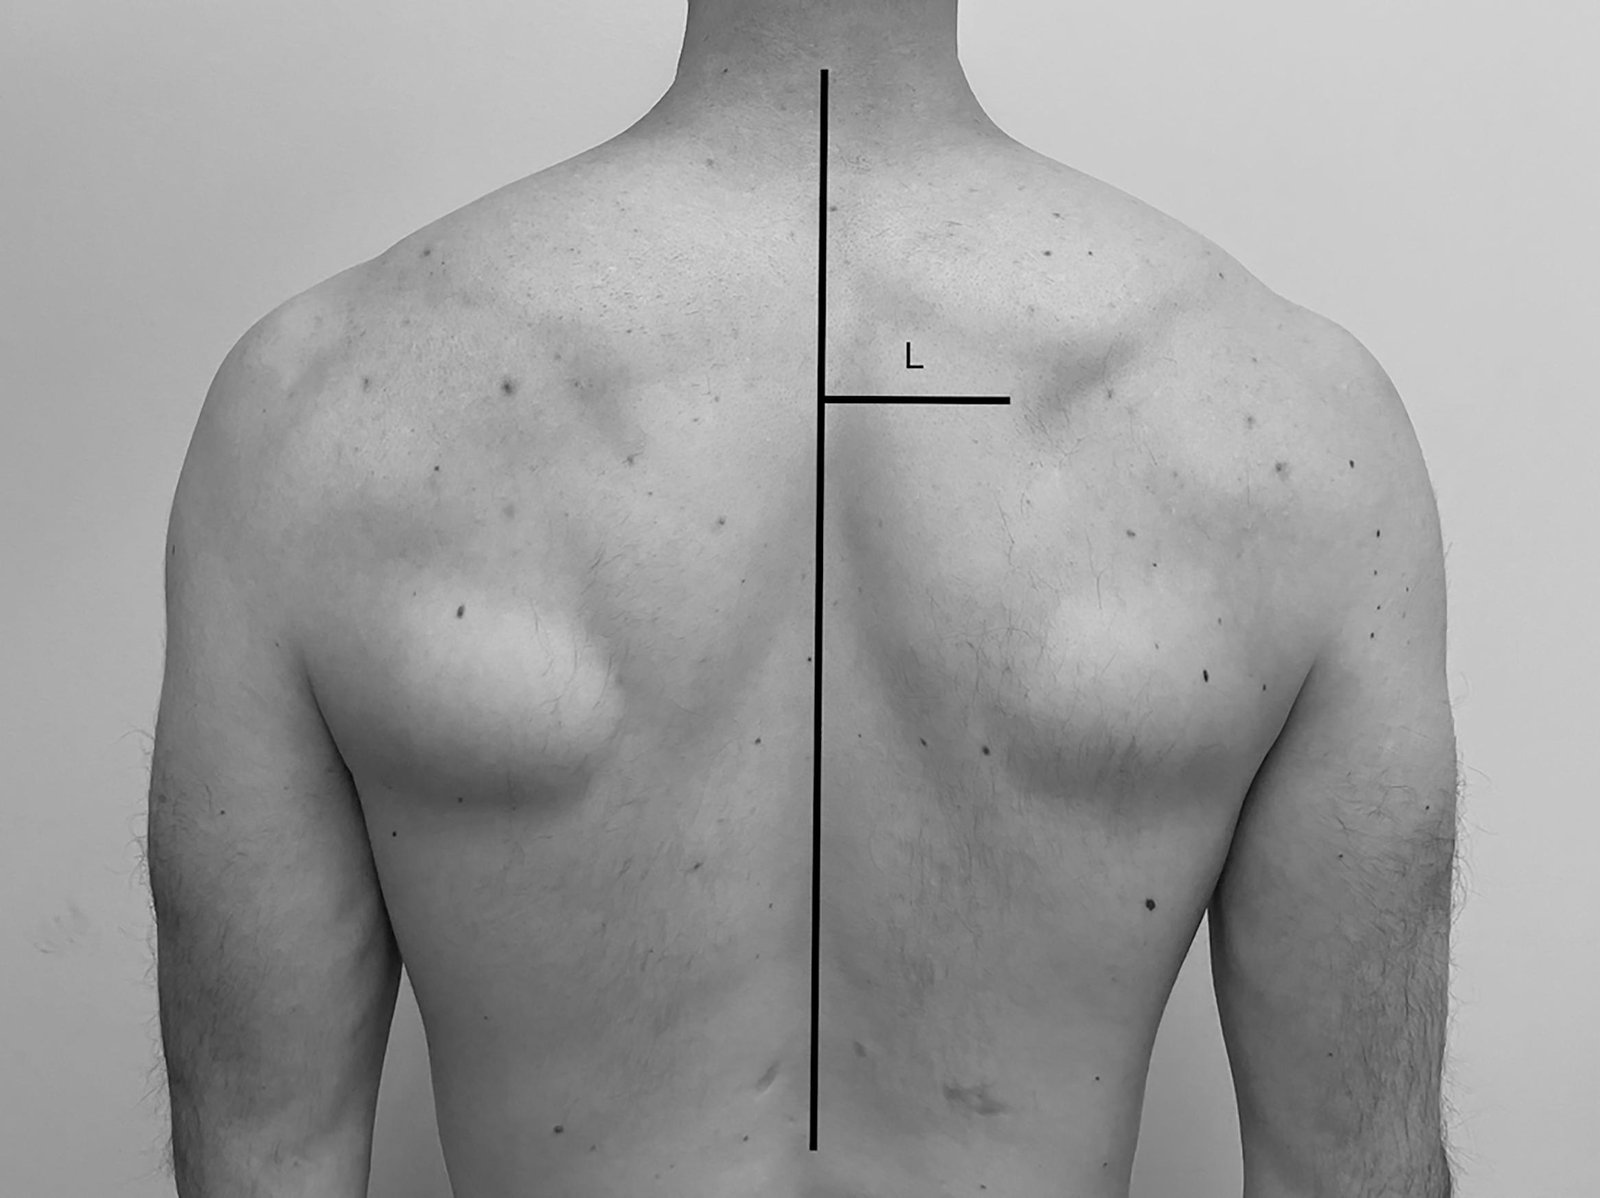

Scapular dyskinesia refers to abnormal movement patterns of the scapula (shoulder blade). It can occur due to various reasons, including muscle weakness, muscle tightness, poor posture, or neurological conditions.

Dr. Ishan Shevate is a physician specializing in orthopedics or sports medicine, who may have expertise in diagnosing and treating conditions related to the musculoskeletal system, including scapular dyskinesia. Treatment for scapular dyskinesia often involves physical therapy to strengthen weak muscles, stretching tight muscles, correcting posture, and improving overall shoulder mechanics. In some cases, other interventions such as injections or surgical procedures may be necessary, depending on the underlying cause and severity of symptoms.